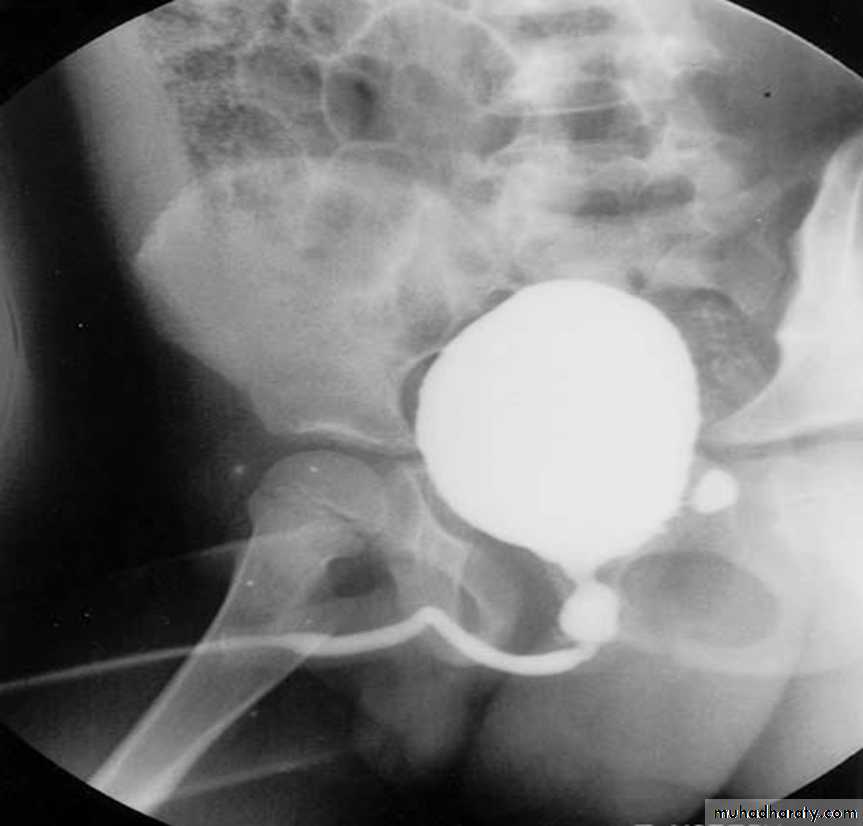

The voiding cystourethrogram (VCUG): the gold standard for reflux detection.Renal Sonography: it is used for serial follow-up of renal growth and development.

Ultrasound: The classic ultrasound findings in patients with PUV include bilateral hydroureteronephrosis, distended bladder, dilated posterior urethra, and a thickened bladder wall.Voiding Cystourethrography VCUG: it defines the anatomy of the bladder, bladder neck, and urethra.

PUV (VCUG)PUV (VCUG)